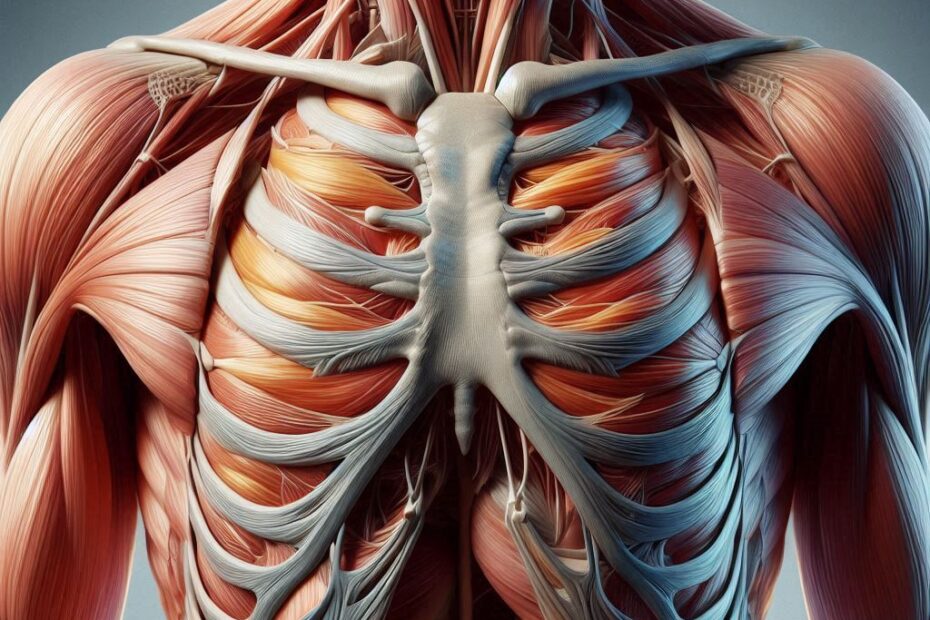

La esperanza contra el cancer o tumores y lo difícil que es.

Dificultades para una célula tumoral. Las vacunas no pueden coincidir en los engranajes del ADN de célula tumoral. Tarea casi imposible o el virus es malo de identificar. Las moléculas pueden ser un alivio, pero… La esperanza contra el cancer o tumores y lo difícil que es.